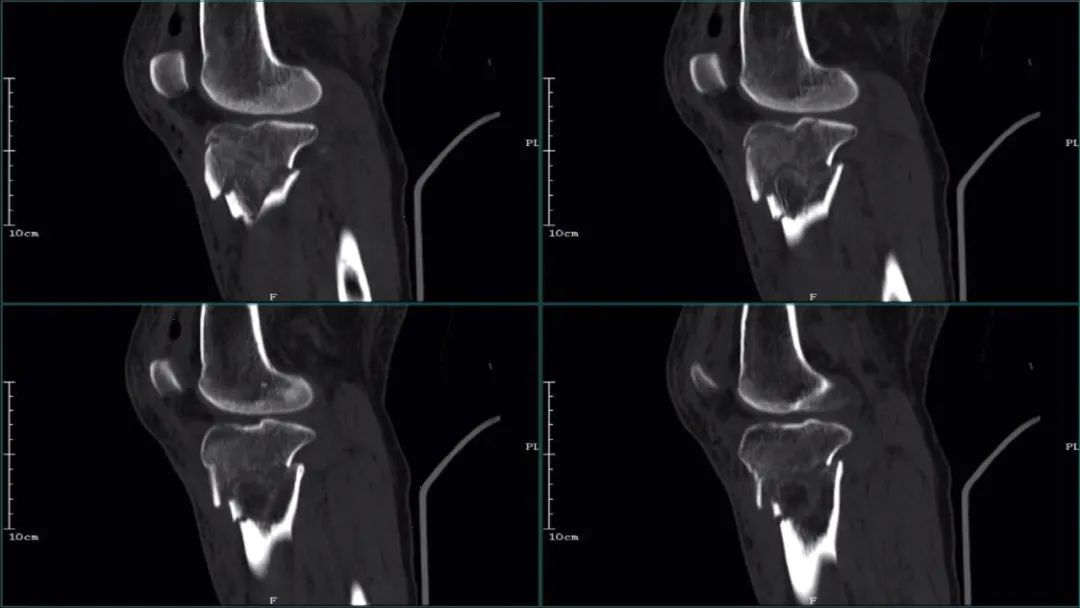

②CT

医学百科网 | YxBaike.Com

CT:胫骨平台内侧粉碎性骨折改变,断端稍移位,周边见多发骨碎片;